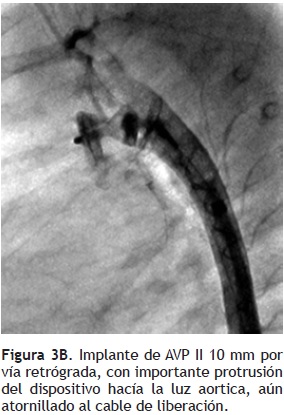

Un implante exitoso del AVP se logró en seis pacientes (85.7%), confirmándose la oclusión angiográfica del CAP, en todos ellos. En uno de nuestros casos (paciente cinco), se optó por no liberar el AVP II, debido que al implantarlo tanto por vía anterógrada como retrógrada, no fue posible obtener la forma del dispositivo dentro de la luz del conducto arterioso, con protrusión del mismo hacía la luz del tronco pulmonar y de la aorta (Figura 3). La paciente, fue enviada finalmente a cirugía. Los tiempos de fluoroscopia y del procedimiento fueron de 5 a 12 minutos (media: 8.5 ± 2.4 minutos) y 40 a 65 minutos (media: 52 ± 9.7 minutos), respectivamente. Como complicación mayor, registramos un evento de sangrado mayor al 10% del volumen circulante, que requirió de hemotransfusión (paciente cinco). La mortalidad fue nula con el procedimiento. Todos los pacientes fueron dados de alta a las 24 horas. En el seguimiento clínico, radiológico y ecocardiográfico a 24 horas, seis meses y un año, de los seis pacientes, observamos una posición adecuada del dispositivo, sin evidencia de fuga residual o datos de obstrucción en la rama pulmonar izquierda (gradiente máximo ecocardiográfico; media de 4.6 ± 1.7 mmHg) o de la aorta descendente (gradiente máximo ecocardiográfico; media de 4.5 ± 0.8 mmHg). El seguimiento total fue de uno a 24 meses (media: 10.6 ± 9.1).

En seis pacientes logramos implantar dispositivos con un diámetro mayor al 50% del calibre mínimo del conducto. Una ventaja potencial del AVP, es la de poderse implantar tanto por la vía anterógrada, como por la retrógrada. En una paciente (caso cinco), con un CAP tubular corto de 4.7 mm de diámetro mínimo, se intentó ocluir inicialmente con un AVP de 10 mm por vía retrógrada y posteriormente con un AVP de 8 mm por vía anterógrada, sin lograr su posicionamiento adecuado, debido a una protrusión significativa del dispositivo hacía la luz de la aorta descendente y de la rama pulmonar izquierda (Figuras 3 A, B y C). Se decidió finalmente no ocluir el CAP y enviarla a cirugía. Se menciona que el AVP no posee un disco de retención aórtico, como el ADO, por lo que puede ser fácilmente centrado dentro del CAP sin protruir hacía la luz de la aorta, y expandirse a su diámetro nominal en forma adecuada, ejerciendo una fuerza radial que lo fija dentro de la luz del conducto.11–13,15 Esta última característica, lo hace particularmente útil en conductos de forma tubular.